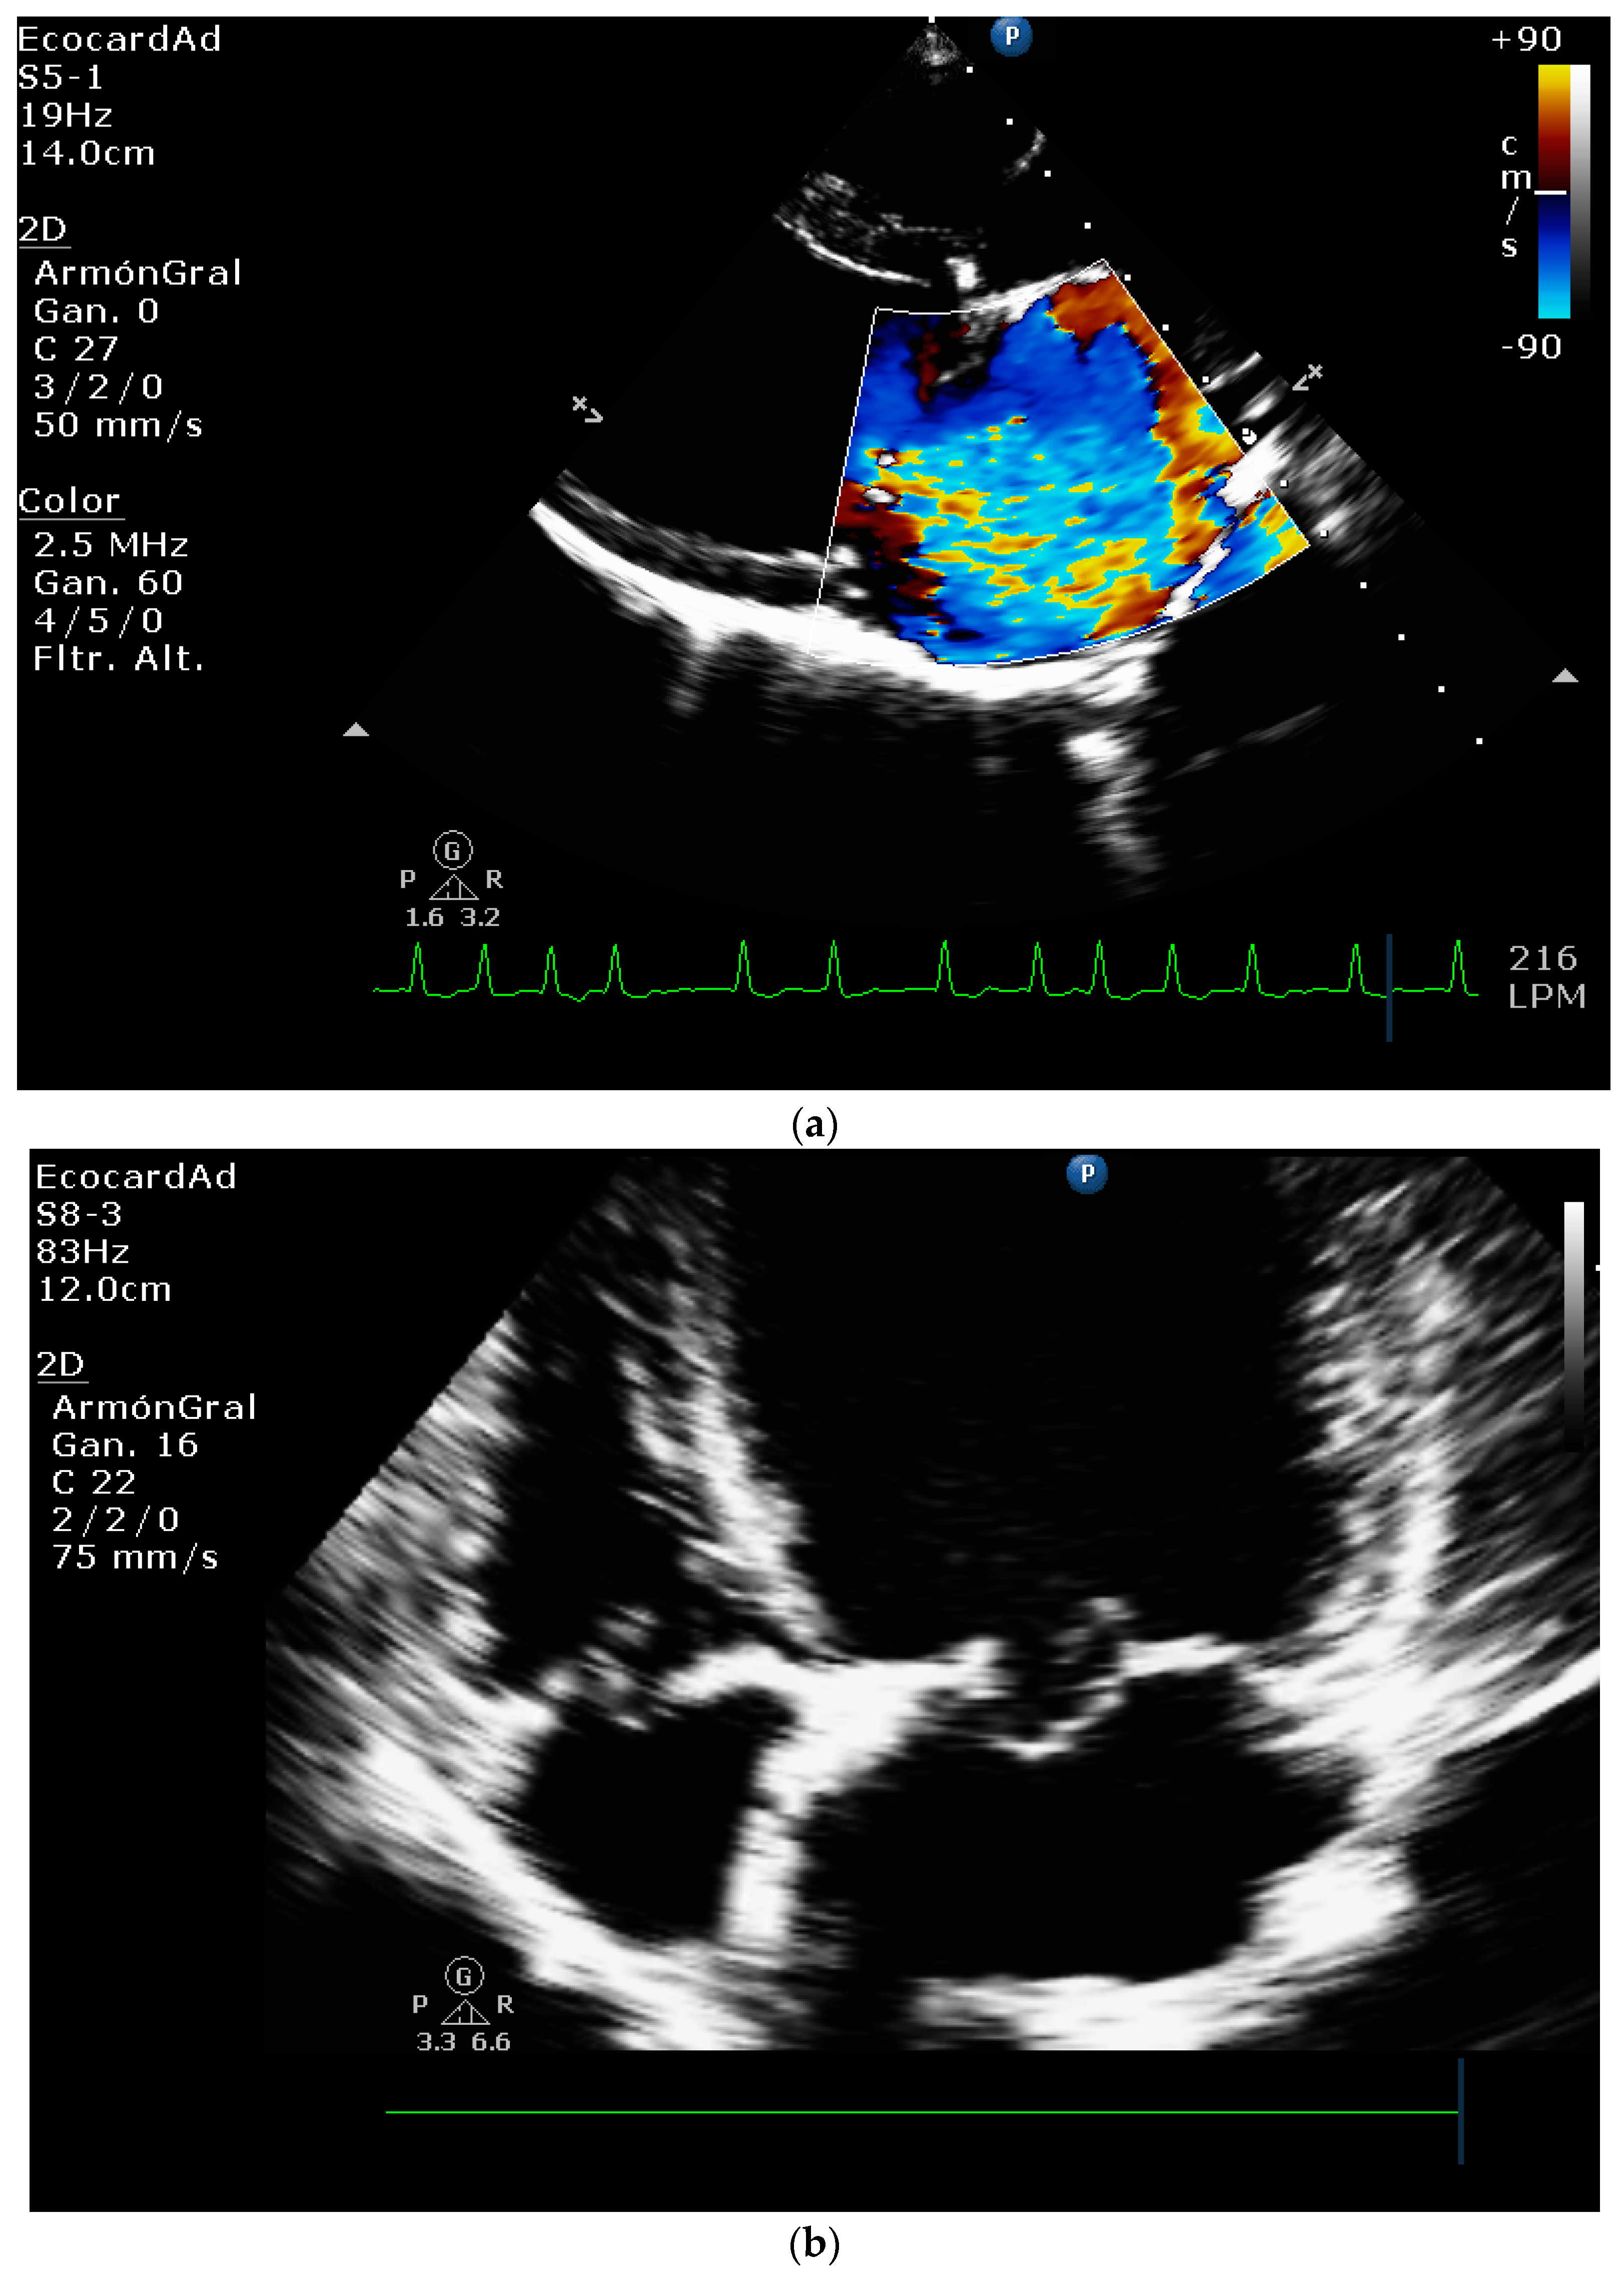

4.4. Comparative Assessment of Mitral Regurgitation Severity

4.5. Mitral Regurgitation Quantification in the Canine Model

4.8.1. Evaluation of the Regurgitant Area

4.8.2. Presence of Vena Contracta

| Color flow imaging of the mitral regurgitation jet area | The most commonly used technique for assessing severity in dogs. The former method is not used in humans as it is not considered reliable for determining the severity of mitral insufficiency. |